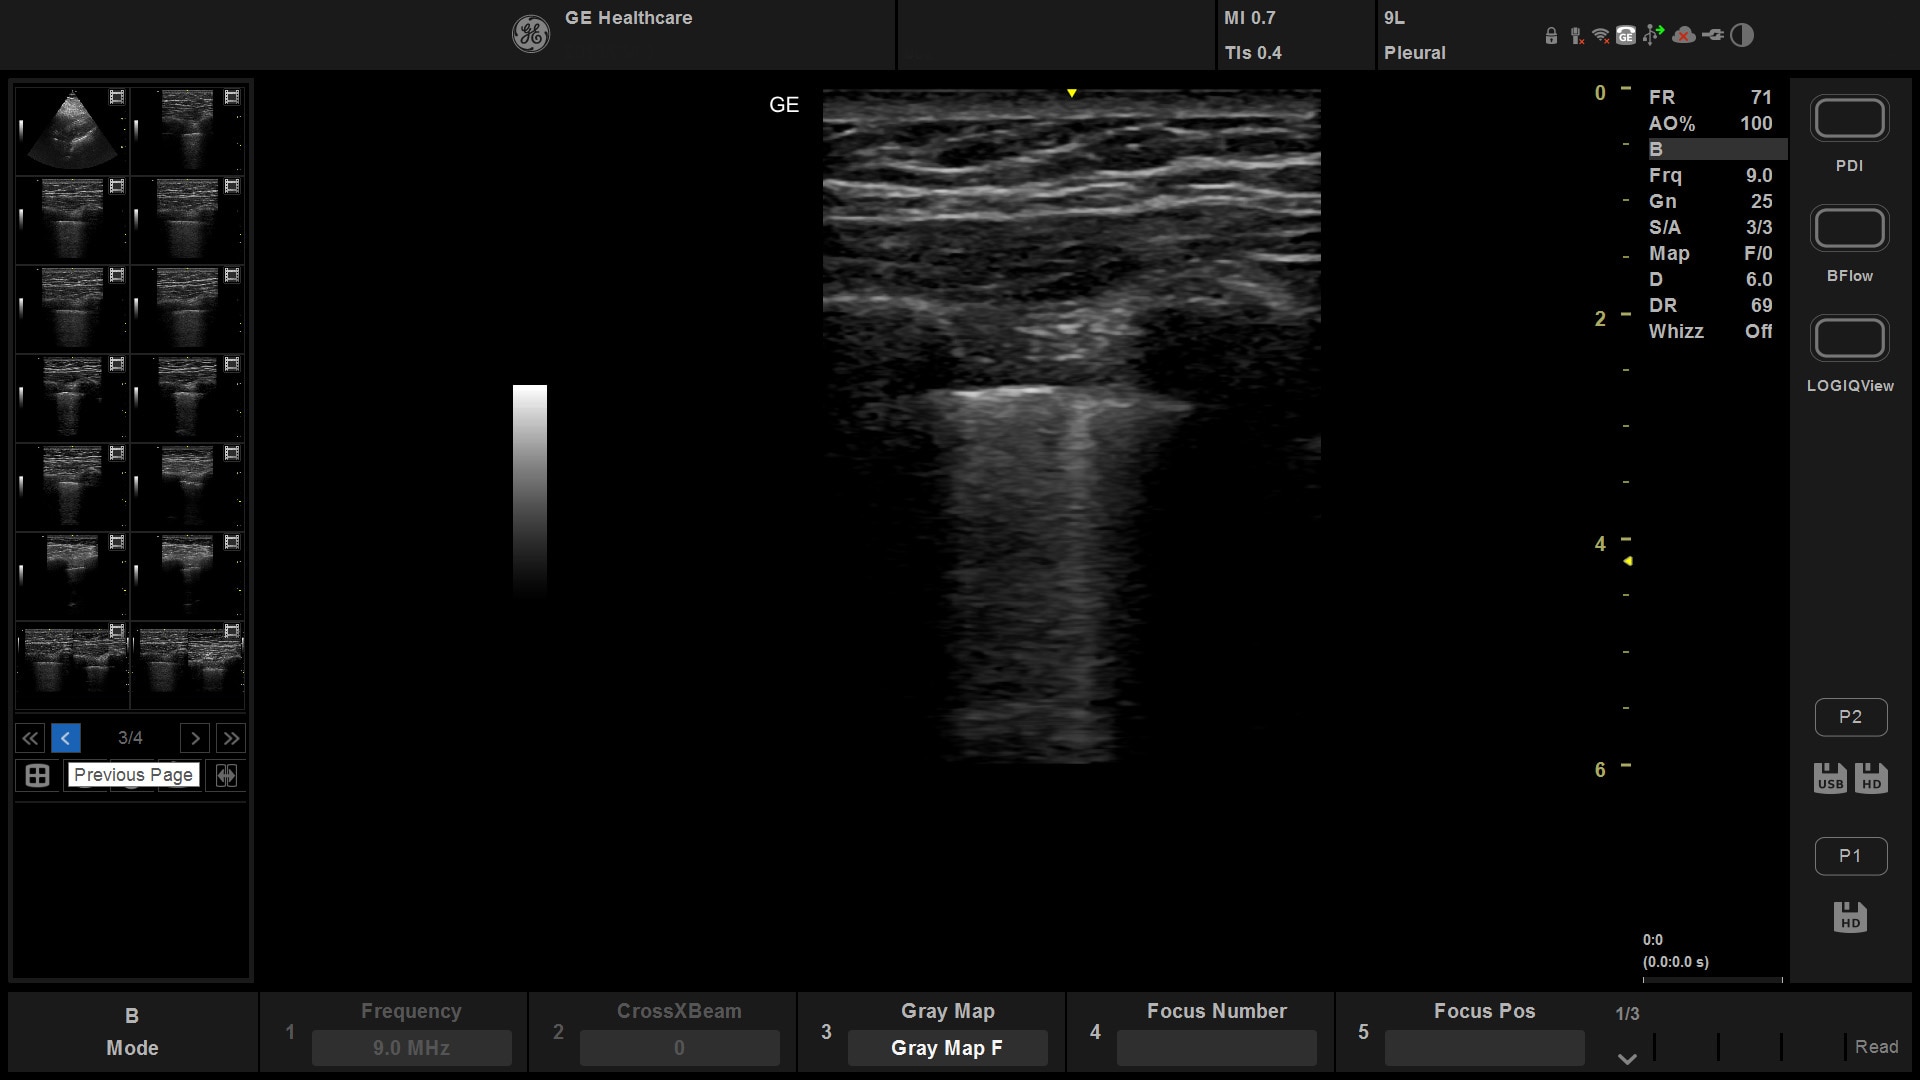

The imaging capability of a console in a portable, lightweight package

Exceptional imaging capability in a compact system

Suited for abdominal, small parts, cardiac, OB/GYN, vascular, and MSK exams

Versana Active delivers the imaging capability of a console in a hand-carried, lightweight package that enables you to actively take your system to your patients, on premises, or remote facilities. The reliable system brings the agility of a laptop unit with the capability for attaching to a cart. Adaptable to cover a broad range of everyday exams, it is easy to carry to clinics, offices, and beyond.